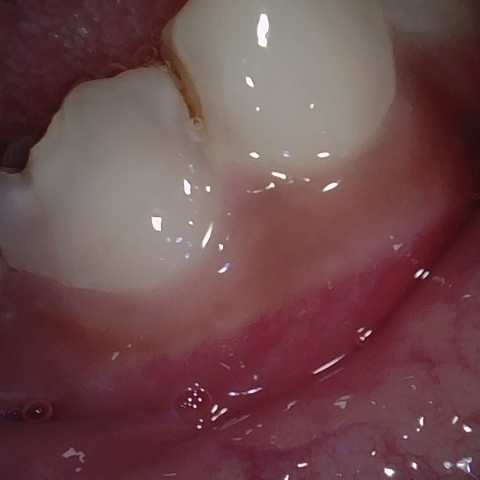

Image 63 / 400

NHD25463

Annotated as "Good"

Original Image Rendering Image